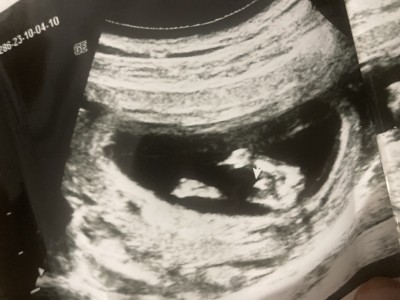

13. haftada  ultrason görüntüsü özelde doktor erkek dedi sonra devlete gitmeye başladım onlar birşey söylemedi Şuan 16. Haftadayım bu görüntü gibi olup kızı olan oldu mı acaba

Sanki erkeğe benziyor

Bencede erkek bu , zaten Dr da erkek demiş bence kafanı karıştırma

Oglandir o, zaten devlet hastanesi cinsiyet söylemiyor

Erkek baksana canım orada başka ne olabilir :)

Oğlumun da ultrason da böyle görmüştüm :)